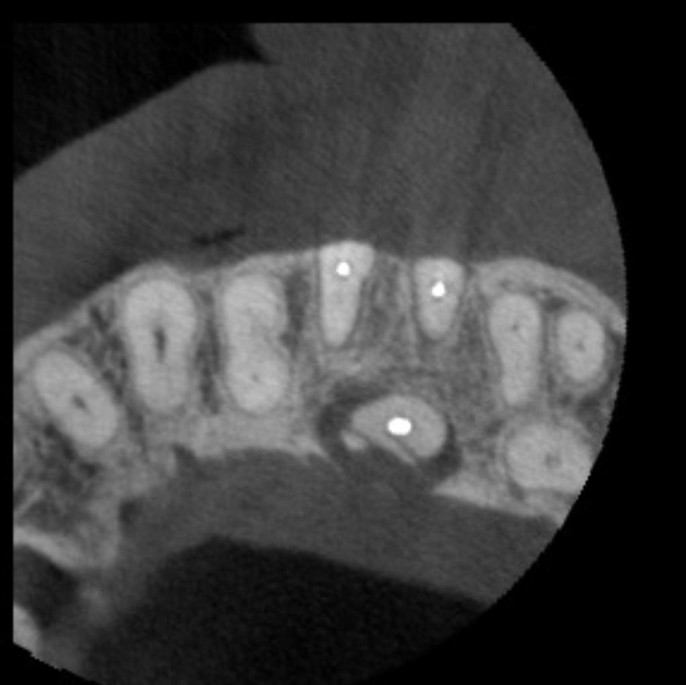

Estudios 3D

- Tomografía volumétrica con técnica de cone beam localizada.

- Tomografía volumétrica con técnica de cone beam para endodoncia. Cortes de 75 Mm

- Tomografía volumétrica con técnica de cone beam Hemiarcada.

- Maxilar.

- Mandibular.